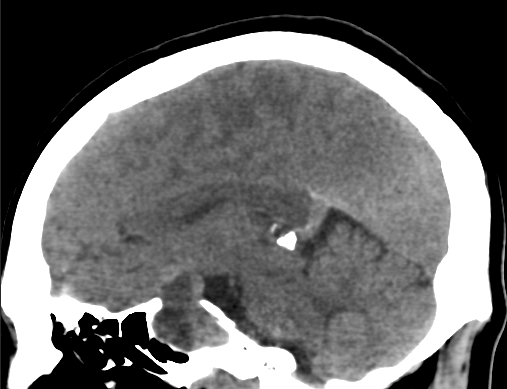

16岁女孩罹患较大侵袭性垂体瘤 压迫眼动脉、视神经等重要部位 视力下降、药石无灵 良性肿瘤为何如此严重? 内镜手术切除病变后,视力好转! 然8年后...